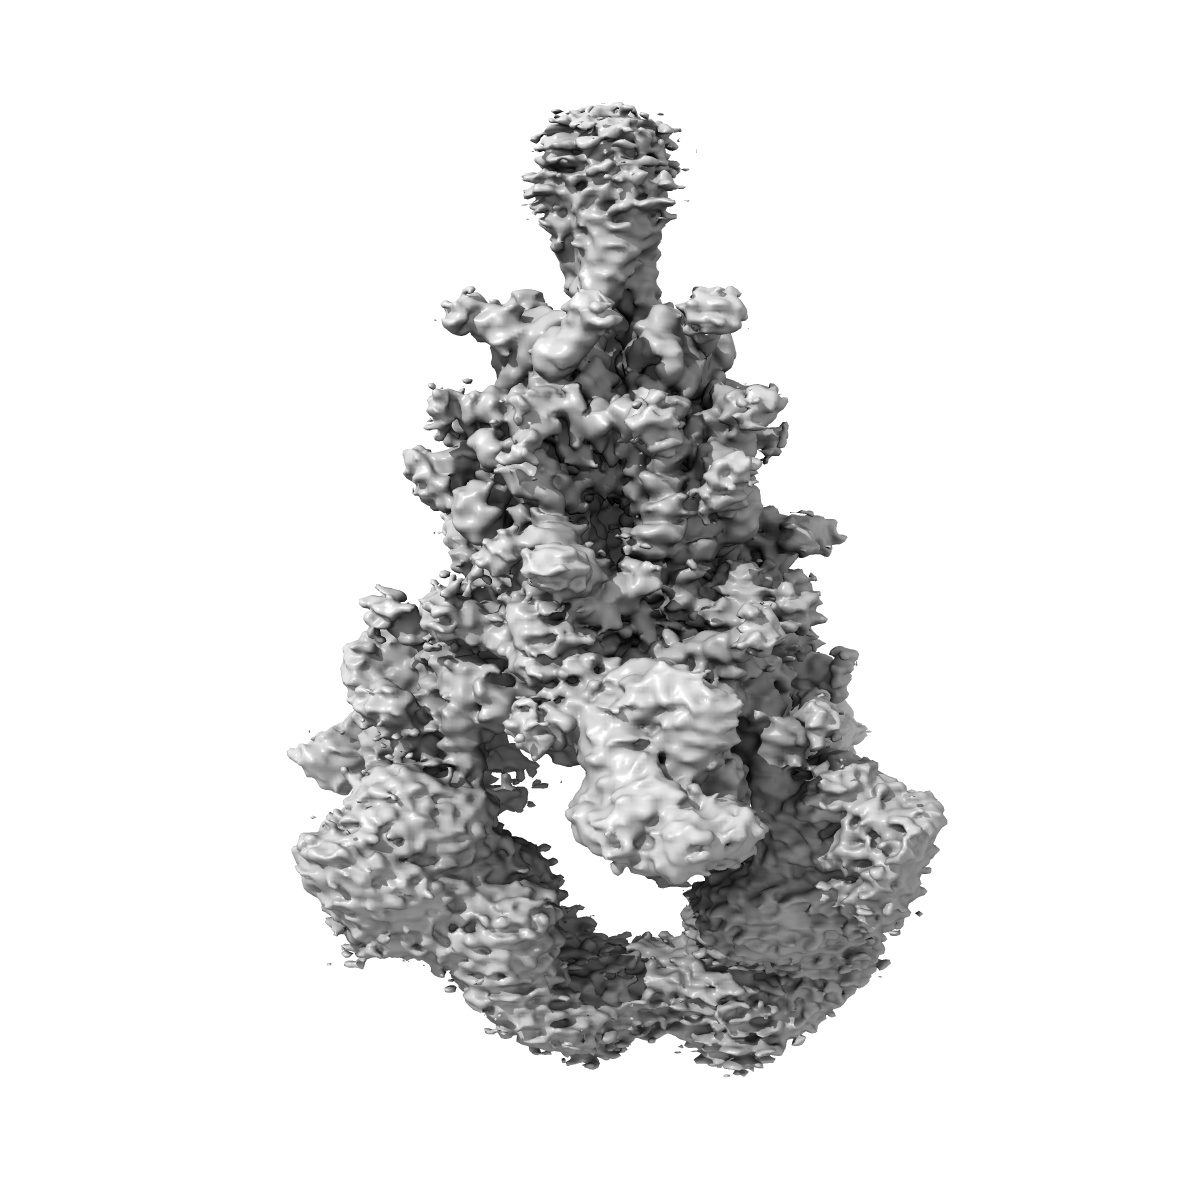

State 2 of SARS-CoV-2 XBB Variant Spike protein trimer complexed with antibody PW5-5

Single-particle3.21 Å

Sample: SARS spike protein (S) in complex with broadly neutralizing antibody PW5-5

Potent and broadly neutralizing antibodies against sarbecoviruses induced by sequential COVID-19 vaccination.